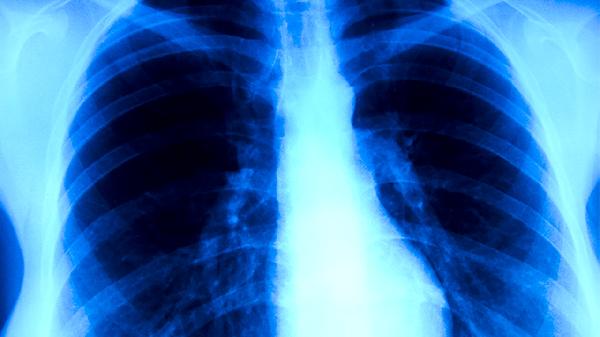

肺结核患者的营养原则

肺结核患者的营养原则主要包括高热量、高蛋白、高维生素、适量矿物质和充足水分摄入。合理的营养支持有助于改善患者免疫功能,促进病灶修复,减少药物不良反应。